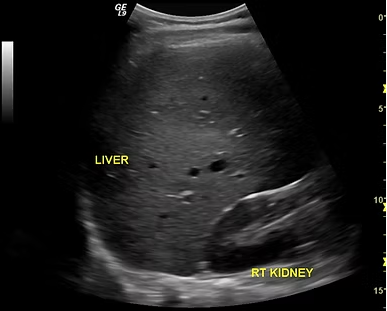

Our medical ultrasound imaging center uses advanced ultrasound technology for safe, non-invasive evaluation of organs, tissues, and blood flow.

Diagnostic ultrasounds require a medical order and include a variety of options such as abdominal, pelvic, thyroid, vascular, musculoskeletal, and obstetric ultrasounds. Whether your physician needs to assess internal structures, monitor blood circulation, or evaluate pregnancy health, our experienced Parker sonographers deliver clear results and compassionate care in a comfortable, welcoming environment.